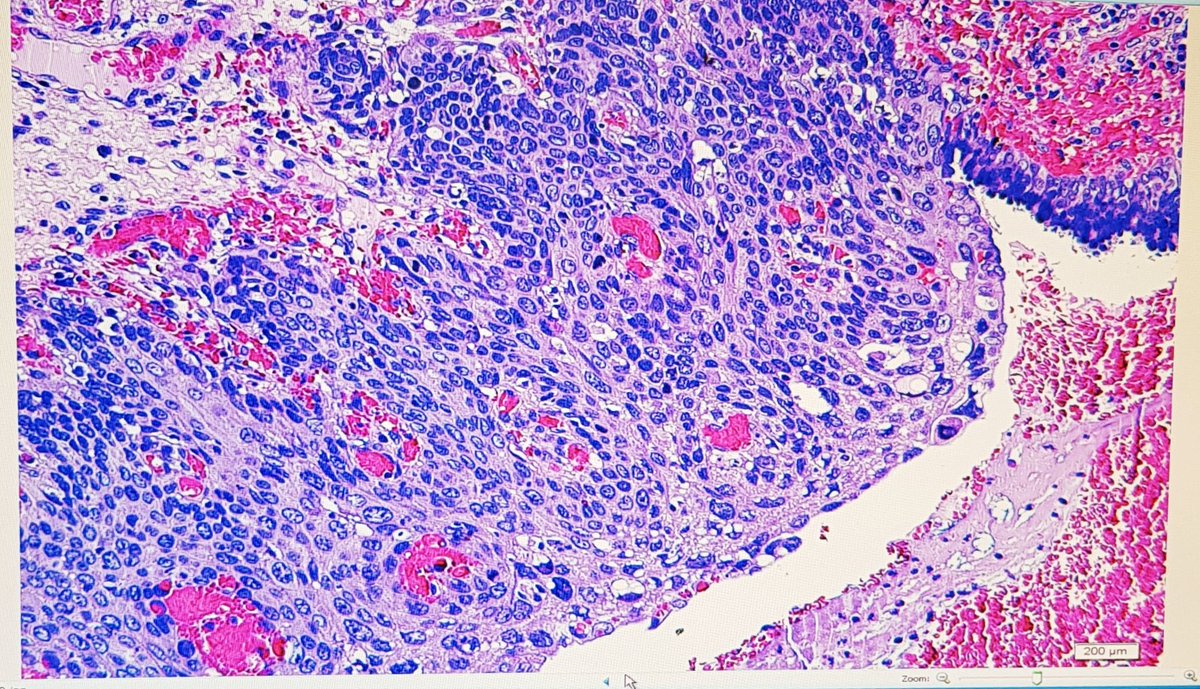

Incredibly thankful and excited to announce that I’ll be joining the faculty @MGHPathology @harvardmed this Spring! Thank you to all my mentors and colleagues here and @PennPathLabMed where I trained as a resident - I learn more from you each day! #gynpath #BreastPath #gupath